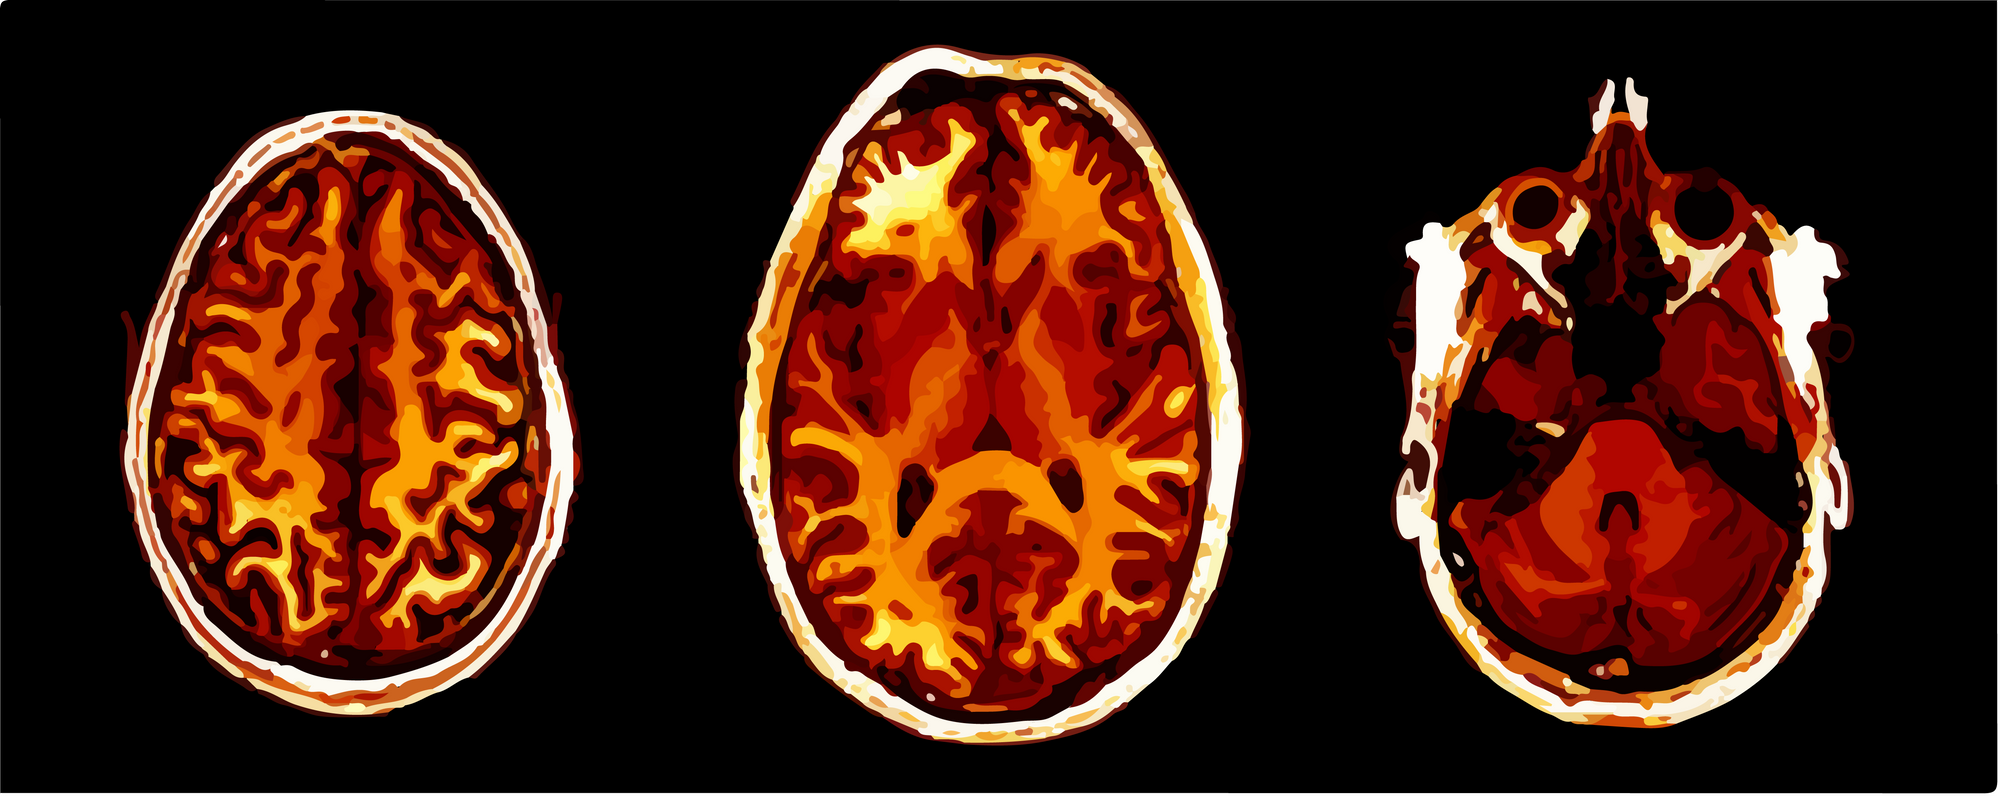

014: Brain Scans

Some visuals from a neuroscience study.

My friend sent in some images of his brain.

These are from a neuroscience research study.

They are T1-weighted structural images of his head 😳.

Beautiful and bizarre.

This was for academic research only (he's fine).